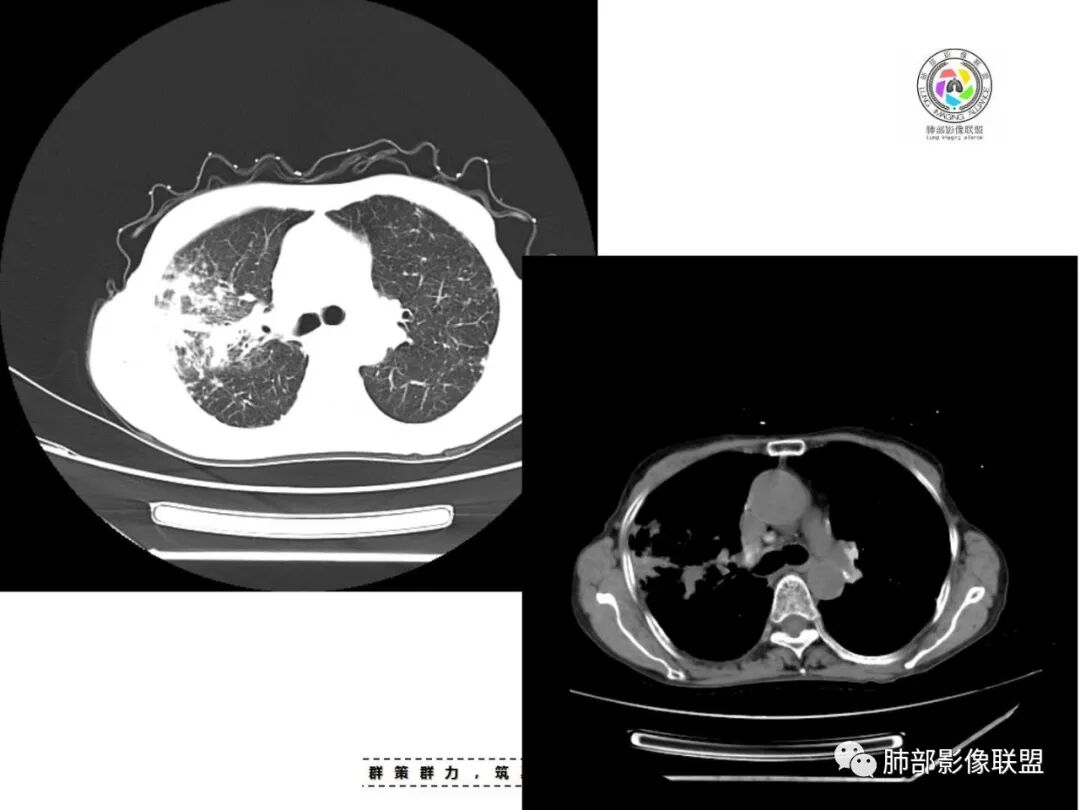

双肺多发片状影,索条影及小结节影,并见少许钙化,右肺上叶为主,主病灶无彭隆,考虑结核可能大

双肺不均匀散在分布斑片状,条索状,斑点状影,边缘部分清晰,可见部分病灶钙化,考虑感染性病变,结核?NTM?详细询问病史,尘肺+结核?

双上肺多发片状、索条影及小结节影,并见少许钙化,右肺上叶后段肿块,后段支气管阻塞,边缘膨隆,双上肺小叶间隔增厚呈多发结节状,胸膜局限性增厚,考虑:1、双肺上叶结核;2、右肺上叶后段腺癌并癌淋。

老年女性,短病程,咳嗽,咳痰为主诉,双肺多发病灶,右上为主,实变,小结节,条索,考虑结核,但小叶间隔增厚,胸膜下多发结节,警惕肿瘤。

女,67,咳嗽咳痰半月,双肺多发病灶,部分钙化,右肺为著,右肺上叶大片实变影,累及胸膜,右肺上叶支气管堵塞,右侧肺门略增大,考虑肺癌,双肺结核。

老年女性,主病灶在右肺上叶,有点散,周围可见卫星灶及少许树芽,双肺多发索条、结节及散在钙化,纵隔及肺门见钙化淋巴结,考虑结核。

双肺多发斑片,索条及结节影,内可见钙化,右肺上叶后段支气管截断,断端圆钝略扩张,双肺门及纵膈淋巴结钙化,双侧胸膜增厚伴钙化。首先考虑结核。右肺上叶亚段气管分叉处结节,警惕肿瘤

老年女性,双肺索条纤维影,右肺上叶散在卫星灶,树芽征,小叶中心融合,右肺后段支气管圆形截断,实变病灶内支气管扩张,考虑结核。

老年女性,病史半个月,两肺上叶为主病灶,多发不规则实变影、条索状影及散在小结节影,首先考虑结核,警惕合并肺癌,尤其是右肺上叶团块实变影。还可以看看重建图像,必要的增强。

患者老年女性,咳嗽、咳痰半月余。查体双肺可闻及痰鸣音。胸部CT:双肺上叶可见多发结节、条索、斑片实变影及小叶间隔增厚,部分见分叶、长毛刺及钙化,表面光滑,纵隔淋巴结有钙化。综合考虑良性病变,结核可能大,鉴别腺癌并癌性淋巴管炎。

老年女性,咳嗽咳痰,双肺散在片状及索条状高密度影,以右肺上叶为主,周围可见结节,实变内可见钙化,纵膈及双肺门可见钙化淋巴结,首先考虑感染性病变,结核可能大,警惕右肺上叶肿瘤并癌性淋巴管炎

双肺多发斑片,索条及结节影,内可见钙化,右肺上叶结节影,空泡,右肺上叶后段支气管截断,断端圆钝略扩张,双肺门及纵隔淋巴结钙化,双侧胸膜增厚伴钙化。首先结核肯定会有,右肺上叶结节,考虑腺癌

老年女性,咳嗽咳痰半月,肺部听诊痰鸣音。影像以右上肺实变?肿块?与支气管关系不清晰;另见两上肺结节、条索,胸膜局部增厚有钙化点,纵隔肺门淋巴结见钙化。综合考虑结核可能性大,注意肺癌。完善增强及支气管镜等检查。

老年女性,咳嗽咳痰半月,双上肺多发条索影,结节影,密度较高,右肺上叶不规则肿块,内有钙化,靠近胸膜下,靠内侧可见斑片影,树芽征,支气管壁增厚,考虑尘肺并肺结核,肺癌待排。

双肺上叶,结节,斑片,条索,大片实变影,支气管远端不通,是不是层面不够啊,后段支气管堵没堵?肺门纵隔淋巴结钙化,常规考虑结核。

双上肺索条,多发边缘清楚的结节,右上肺结节灶,无连续层面,不能判断支气管是否堵塞,双肺多发钙化,考虑结核,建议气管镜

常规考虑结核(鉴别尘肺合并结核,职业史?),老年人还要排除恶性(原发肺癌或者转移,需要结合病史与肿瘤标志物,必要时穿刺活检或支气管镜检)

双肺多发条索状,结节病灶,以右肺显著,部分病灶有爬树征,树芽征,未见明显钙化,纵隔淋巴结增大钙化,常规考虑结核,不能排除肺癌,建议增强和支气管镜检查

两肺上叶多发索片小结节影,部分密度较高,中央间质和周围间质都增厚,肺门纵隔淋巴结肿大钙化,基础疾病考虑有尘肺或陈旧结核,需结合相关病史;右肺上叶见斑片点片状模糊影,部分树芽征上叶后段局部细支气管闭塞,考虑感染,结核可能性大,右肺上叶后段病灶实变成团块状,密度低于胸壁肌肉,首先还是考虑结核肉芽肿,治疗后复查除外合并肿瘤可能。

老年女性,67岁,咳嗽、咳痰半月余。双肺可闻及痰鸣音。

胸部CT:双肺上叶多发小结节,沿胸膜下、支气管血管束分布。右上肺斑片实变影、索条影及小叶间隔不均匀增厚,支气管枯枝征?纵隔淋巴结多发肿大,部分有钙化。综合考虑:结节病?尘肺?鉴别:腺癌并癌淋。

1.双肺片状影、大小不等斑片影、结节影、树芽等,病灶密度偏高多钙化。

2.病灶上肺为主,胸膜下分布为主。双肺病灶明显不对称,右肺块状影较大。

3.纤维条索影广泛杂乱、牵拉,横向分布为主,这点给人也印象很深!

4.纵隔轻度右移。双肺门纵隔淋巴结增大钙化。

5.老年女性患者,咳嗽咳痰半月余